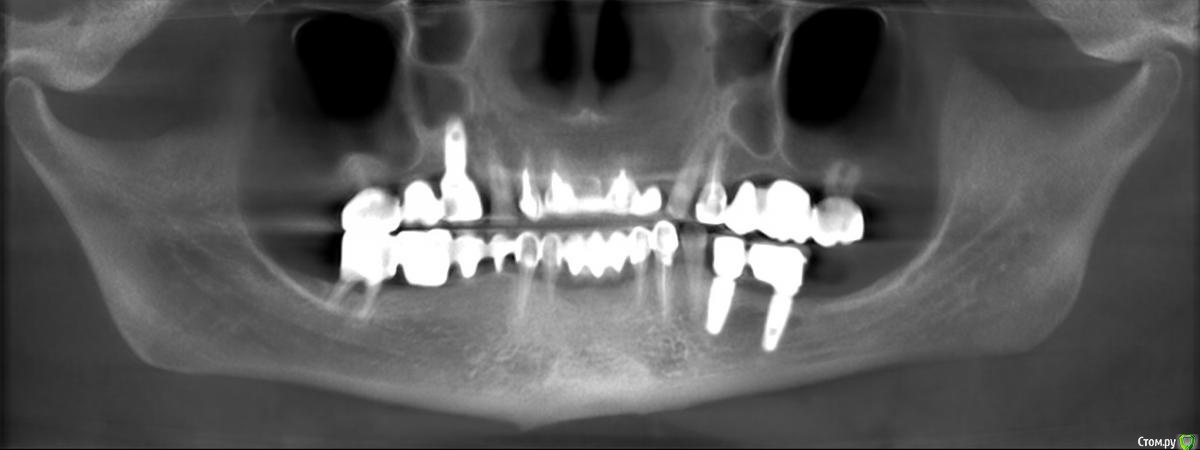

red_butler Опубликовано 24 января, 2016 Поделиться Опубликовано 24 января, 2016 Есть обычная панорама?3.2 4.2 4.7 на выход Ссылка на комментарий

DimaKoleso Опубликовано 24 января, 2016 Автор Поделиться Опубликовано 24 января, 2016 А что по поводу 27 и 17? Ссылка на комментарий

red_butler Опубликовано 24 января, 2016 Поделиться Опубликовано 24 января, 2016 А что по поводу 27 и 17?По вашему снимку, видно только, что эти зубы есть Ссылка на комментарий

Ronin Опубликовано 5 февраля, 2016 Поделиться Опубликовано 5 февраля, 2016 Доктора, вот такая пациентка пришла. Что бы вы сделали?Балка возможна при сильном желании, локаторы теже, или на шариках, если доставить имплантатов, на культевых аттачменах, если хотим что-то оставить своего, бюгелёк даже можно, после оценки КЛКТ, конечно все это при всех удачных аспектах и оговорках, а также правильном планировании и понимании финансов)) Ссылка на комментарий